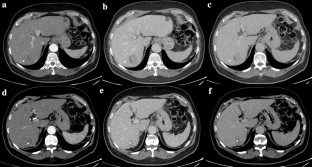

Fig. 1